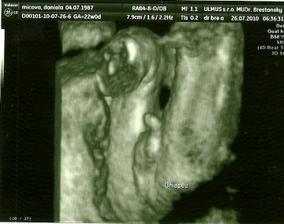

niekedy tie tri D neboli tak ako teraz mám len z obyčajného tzv.ČB